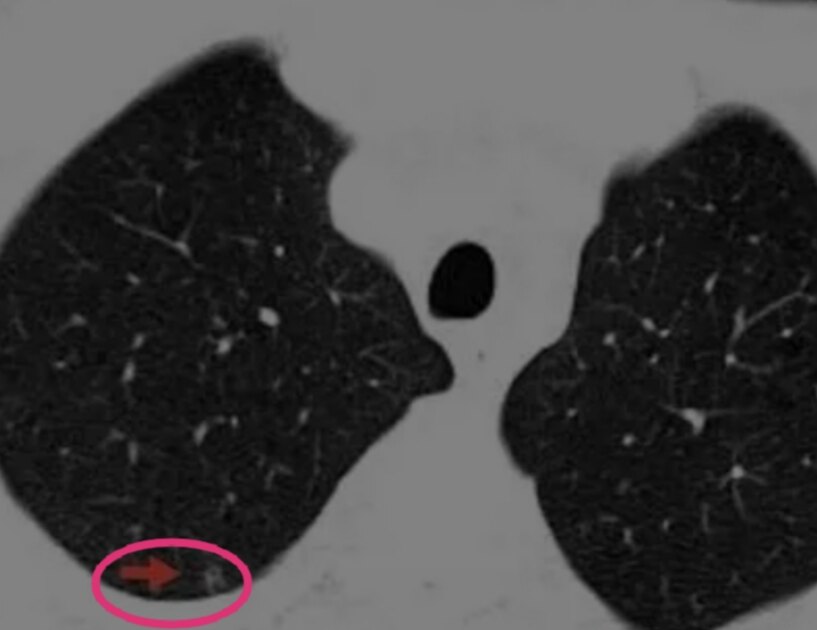

右下肺后段肺部微小实性结节

此为实性结节,5mm,没有毛刺征、胸膜凹陷征及血管弯曲等任何肿瘤的特征性表现。单凭这个CT,任何一个医生或者人工智能AI,都可能会认为这个结节良性可能大,无法确认这个结节是肺癌。

这个时候,就需要通过患者的临床特点和连续动态胸部CT检查结果:肺部结节发生发展趋势来判断肺结节良恶性了。